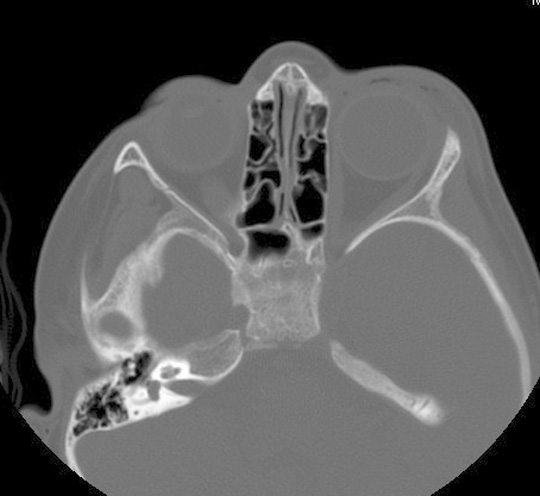

Identify the ethmoid sinus. Click the image for labeling.